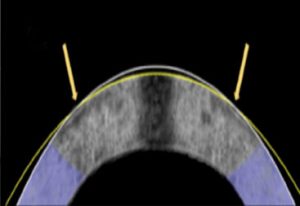

此技術採用特製的鉑金隱形眼鏡作為電極,放置在角膜上方。 當施加微弱電流時,角膜的酸鹼值會改變,令其短暫軟化並按照鏡片形狀重塑。 電流停止後酸鹼值隨即回復正常,角膜亦會重新硬化並維持新形狀。